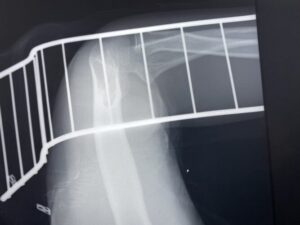

さわやか千葉県民プラザ(上腕骨外科頸骨折)

第13回整骨研究会「賜恩」研修会開催

さわやか千葉県民プラザ(上腕骨外科系骨折)

春日部市市民活動センター(上腕骨顆上骨折)

第28回整骨研究会「賜恩」研修会開催